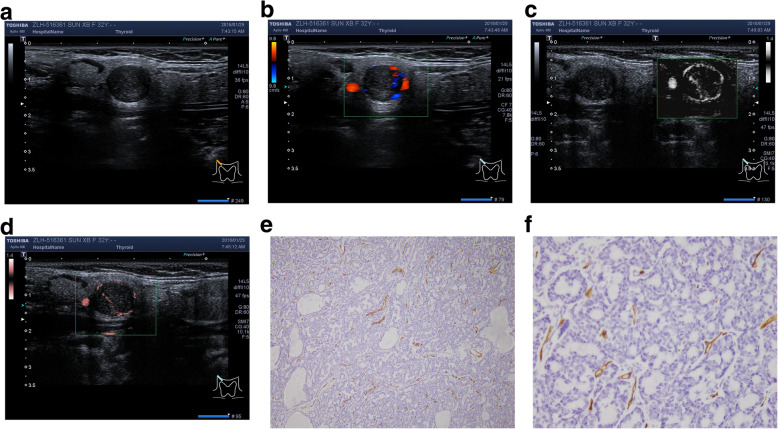

BCA group

Sixteen patients have18 masses of BCA (7.2%). In them, 2 patients have ipsilateral multiple tumors, the represent images were shown in Fig. 3.

Fig. 3.

Represent BCA case from left parotid gland. a. Conventional ultrasound image; b. CDFI: punctate or fine rod vessels, Mixed distribution, Alder 3; c. mSMI and d. cSMI: dense streak blood stream, Mixed distribution, Alder 3. VIby cSMI:18.1; e. MVD by IHC (× 100); f. MVD by IHC: 62 (× 400)

WT group

Sixty-five patients had 83 masses of WT (33.3%). In them, 11 patients had ipsilateral multiple tumors, 7 cases have bilateral solitary tumor, the represent images were shown in Fig. 4.

Fig. 4.

Represent WT case from right parotid gland. a. Conventional ultrasound image; b. CDFI: 3–4 punctate blood flow, Peripheral distribution, Alder 2; c. mSMI and d. cSMI: Mixed distribution, Alder 3. VIby cSMI:7.4; e. MVD by IHC (× 100); f. MVD by IHC: 38 (× 400)